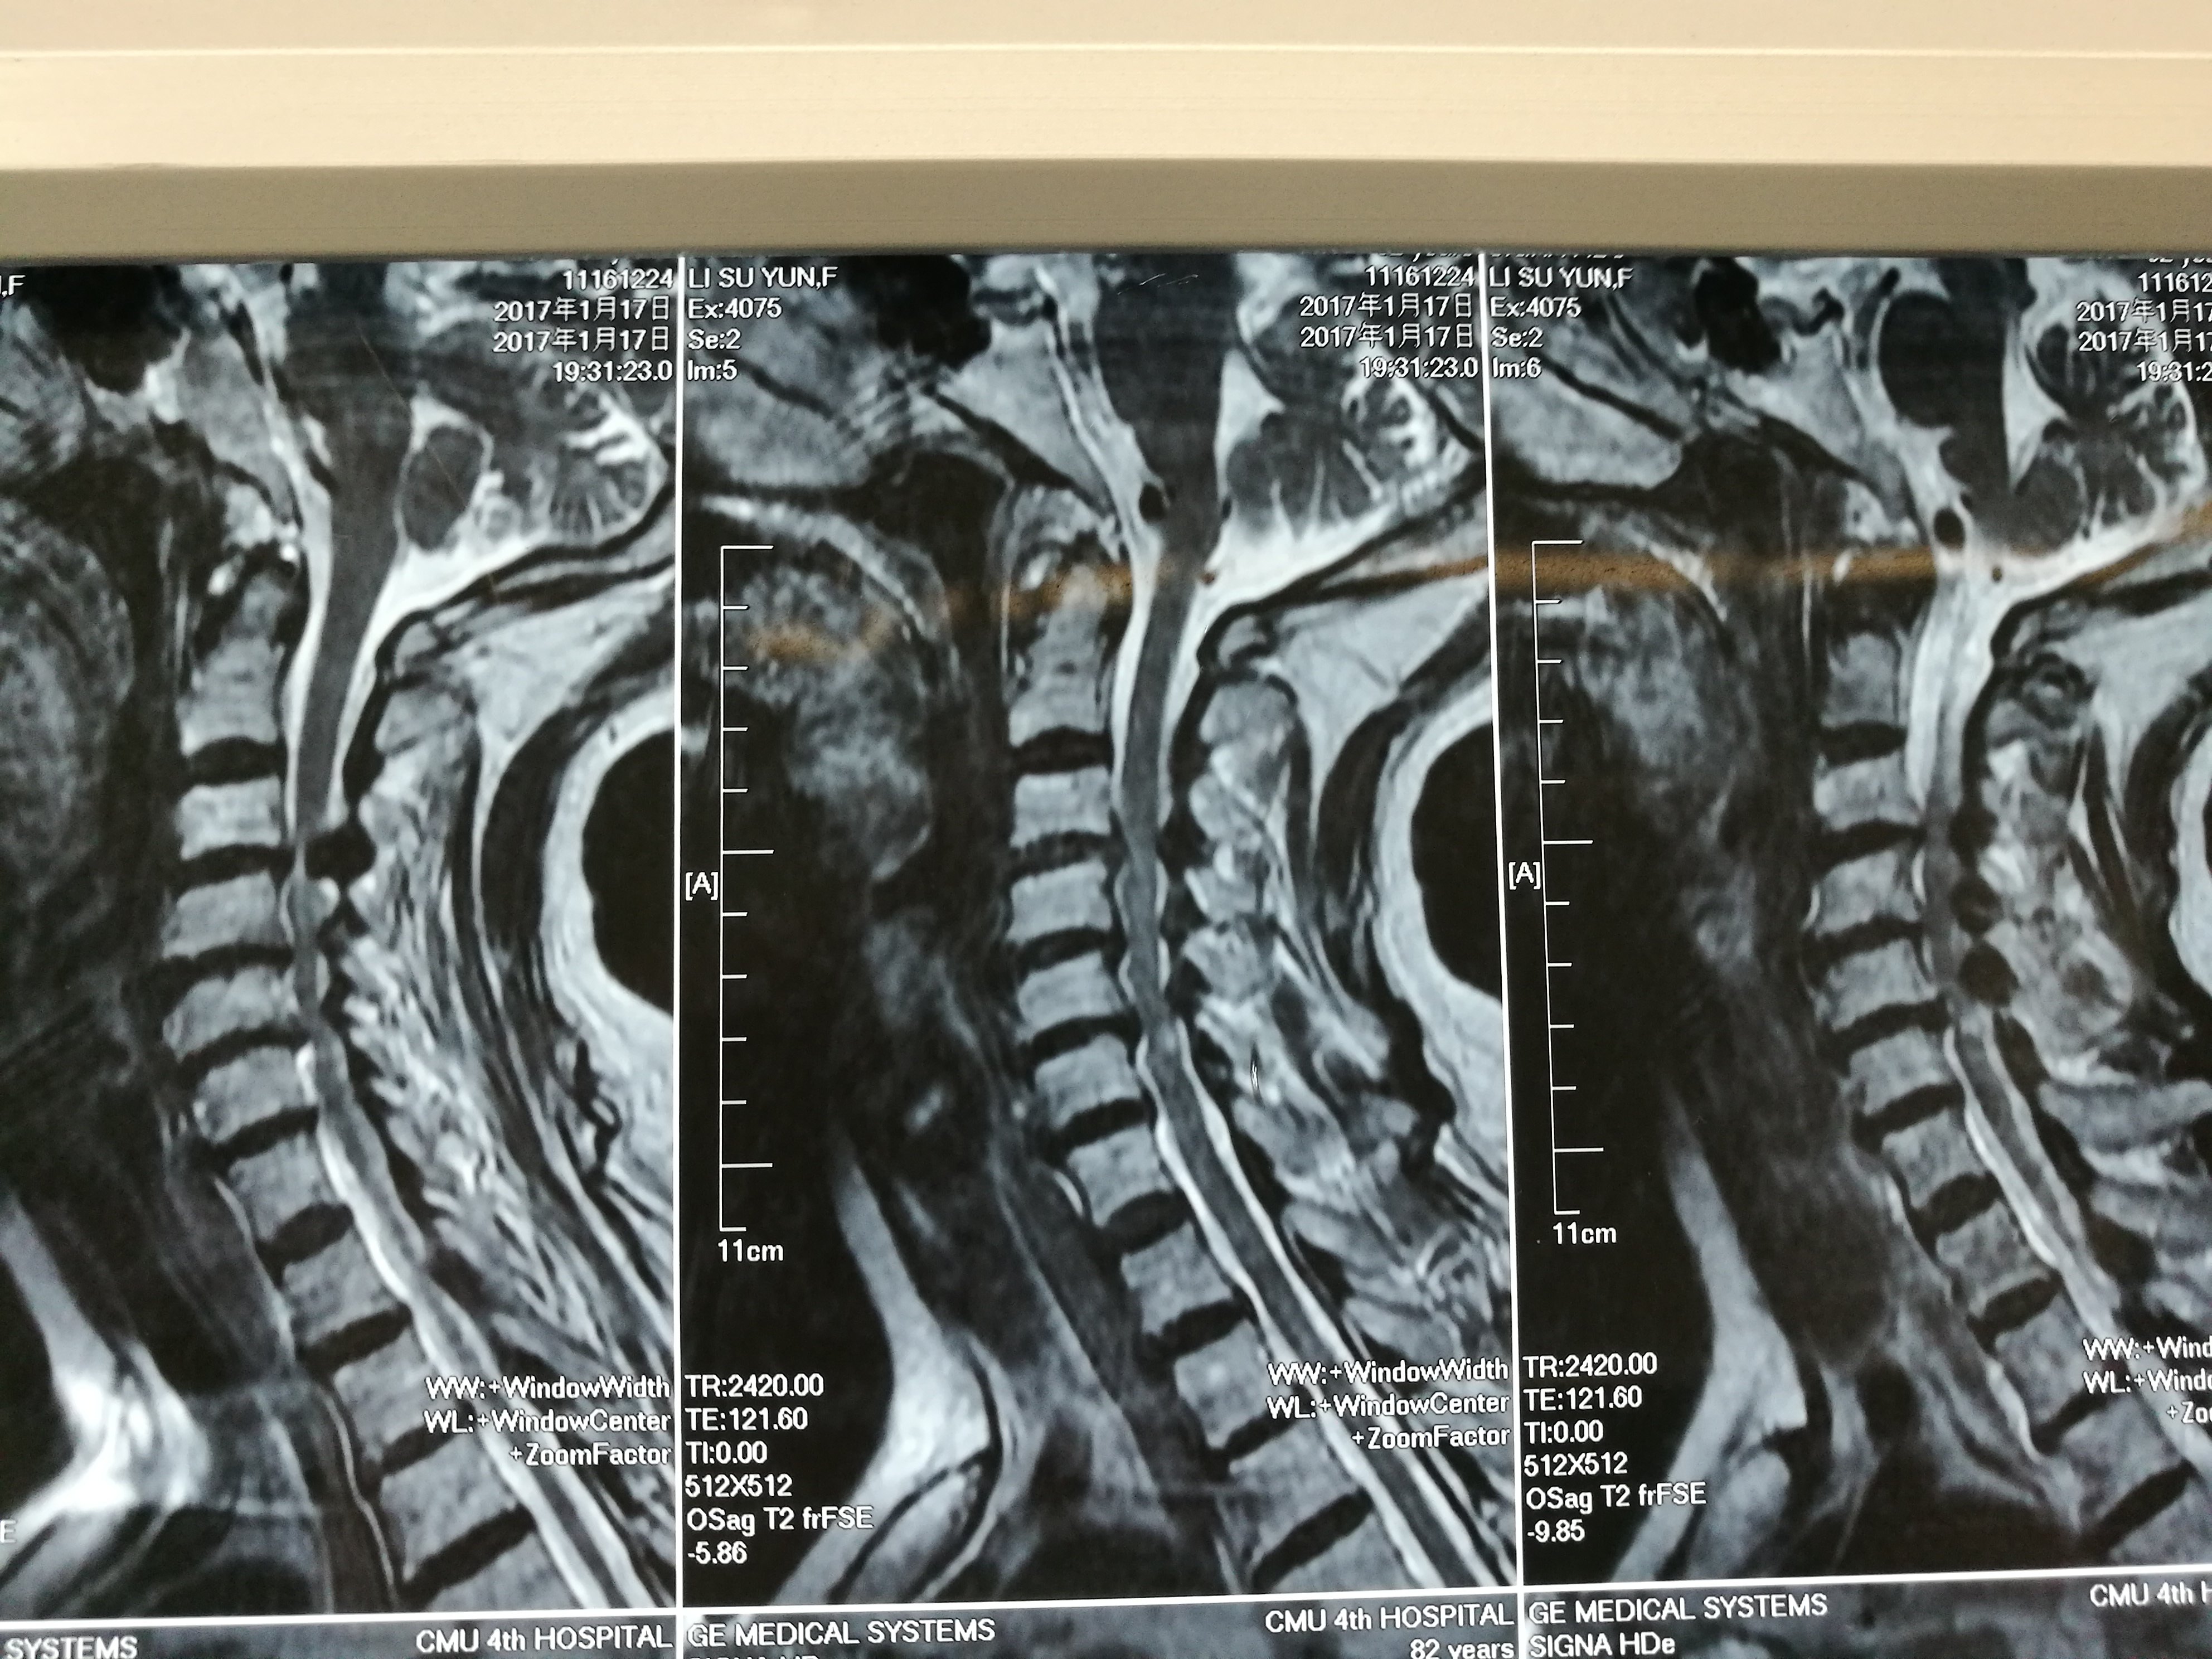

颈椎病,椎管狭窄,黄韧带钙化,神经受压,四肢不全瘫 - 好大夫在线

2018年11月21日颈椎mri提示颈5-6,颈6-7椎间盘突出并黄韧带肥厚.